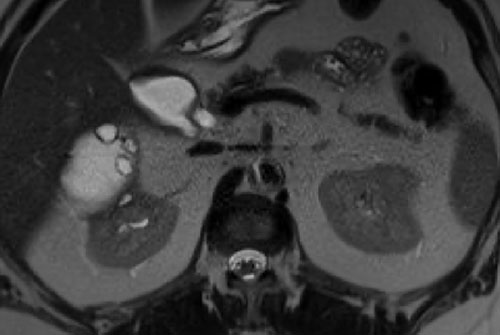

Có một khối dạng nang ở thận phải với nhiều (> 4) vách ngăn mỏng, nhẵn, có ngấm thuốc.

Tổn thương được phân loại là Bosniak IIF.